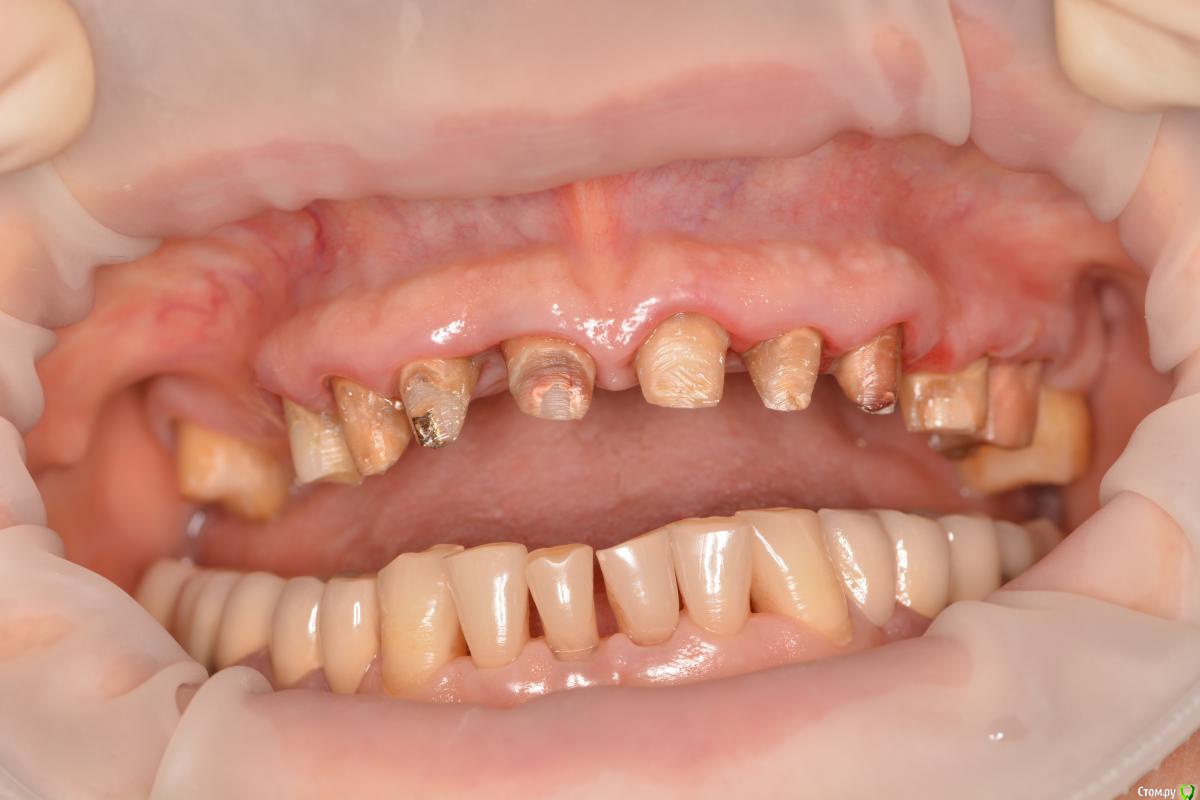

Alexandr1984 Опубликовано 29 марта, 2016 Поделиться Опубликовано 29 марта, 2016 Коллеги, что можно здесь сделать? Речь о верхней челюсти.Пациент родственник. Хотелось бы добиться наилучшей эстетики, особенно во фронте. Ранее стоял металлокерамический мост (подкова). более 15 лет. Можно ли протезировать одиночками?Мысль такая: зубы были шинированы мостом, возможно связочный аппарат частично атрофировался. Не появится ли подвижность при протезировании одиночными коронками? В 1-м сегменте планируется имплантация с синусом. Применим ли имакс к этим зубам? если да, то как фиксировать под десной по адгезивному протоколу? И что делать с темным цветом культей? заранее спасибо) Ссылка на комментарий

Freelancer1981 Опубликовано 29 марта, 2016 Поделиться Опубликовано 29 марта, 2016 (изменено) Снимки нужны,орпеделение цс,вакспа,мокап,зубы,что были под коронками придется восстанавливать,т.к.видно что перепреп,вкладки или адгезивно на стекловолокне.Можно разбить работу,сделать верх мокап длительного ношения и заняться низом,а потом перейти к верх.зубам.Тем более там планируется синус.Верхние коронки скорее всего фронт сделал бы циркон с облицовкой,если хотите эстетику. Изменено 29 марта, 2016 пользователем Freelancer1981 Ссылка на комментарий

Карен Аванесов Опубликовано 30 марта, 2016 Поделиться Опубликовано 30 марта, 2016 С такой местами конусностью и низкой высотой культей, плюс подсыревшим местами дентином, и передавленным местами подковой пародонтом, с надежной фиксацией единичек и здоровьем пародонта будут проблемы. Все делается в комплексе. и еще как вы пресс с коффером то при такой ситуации будете фиксировать? Ссылка на комментарий